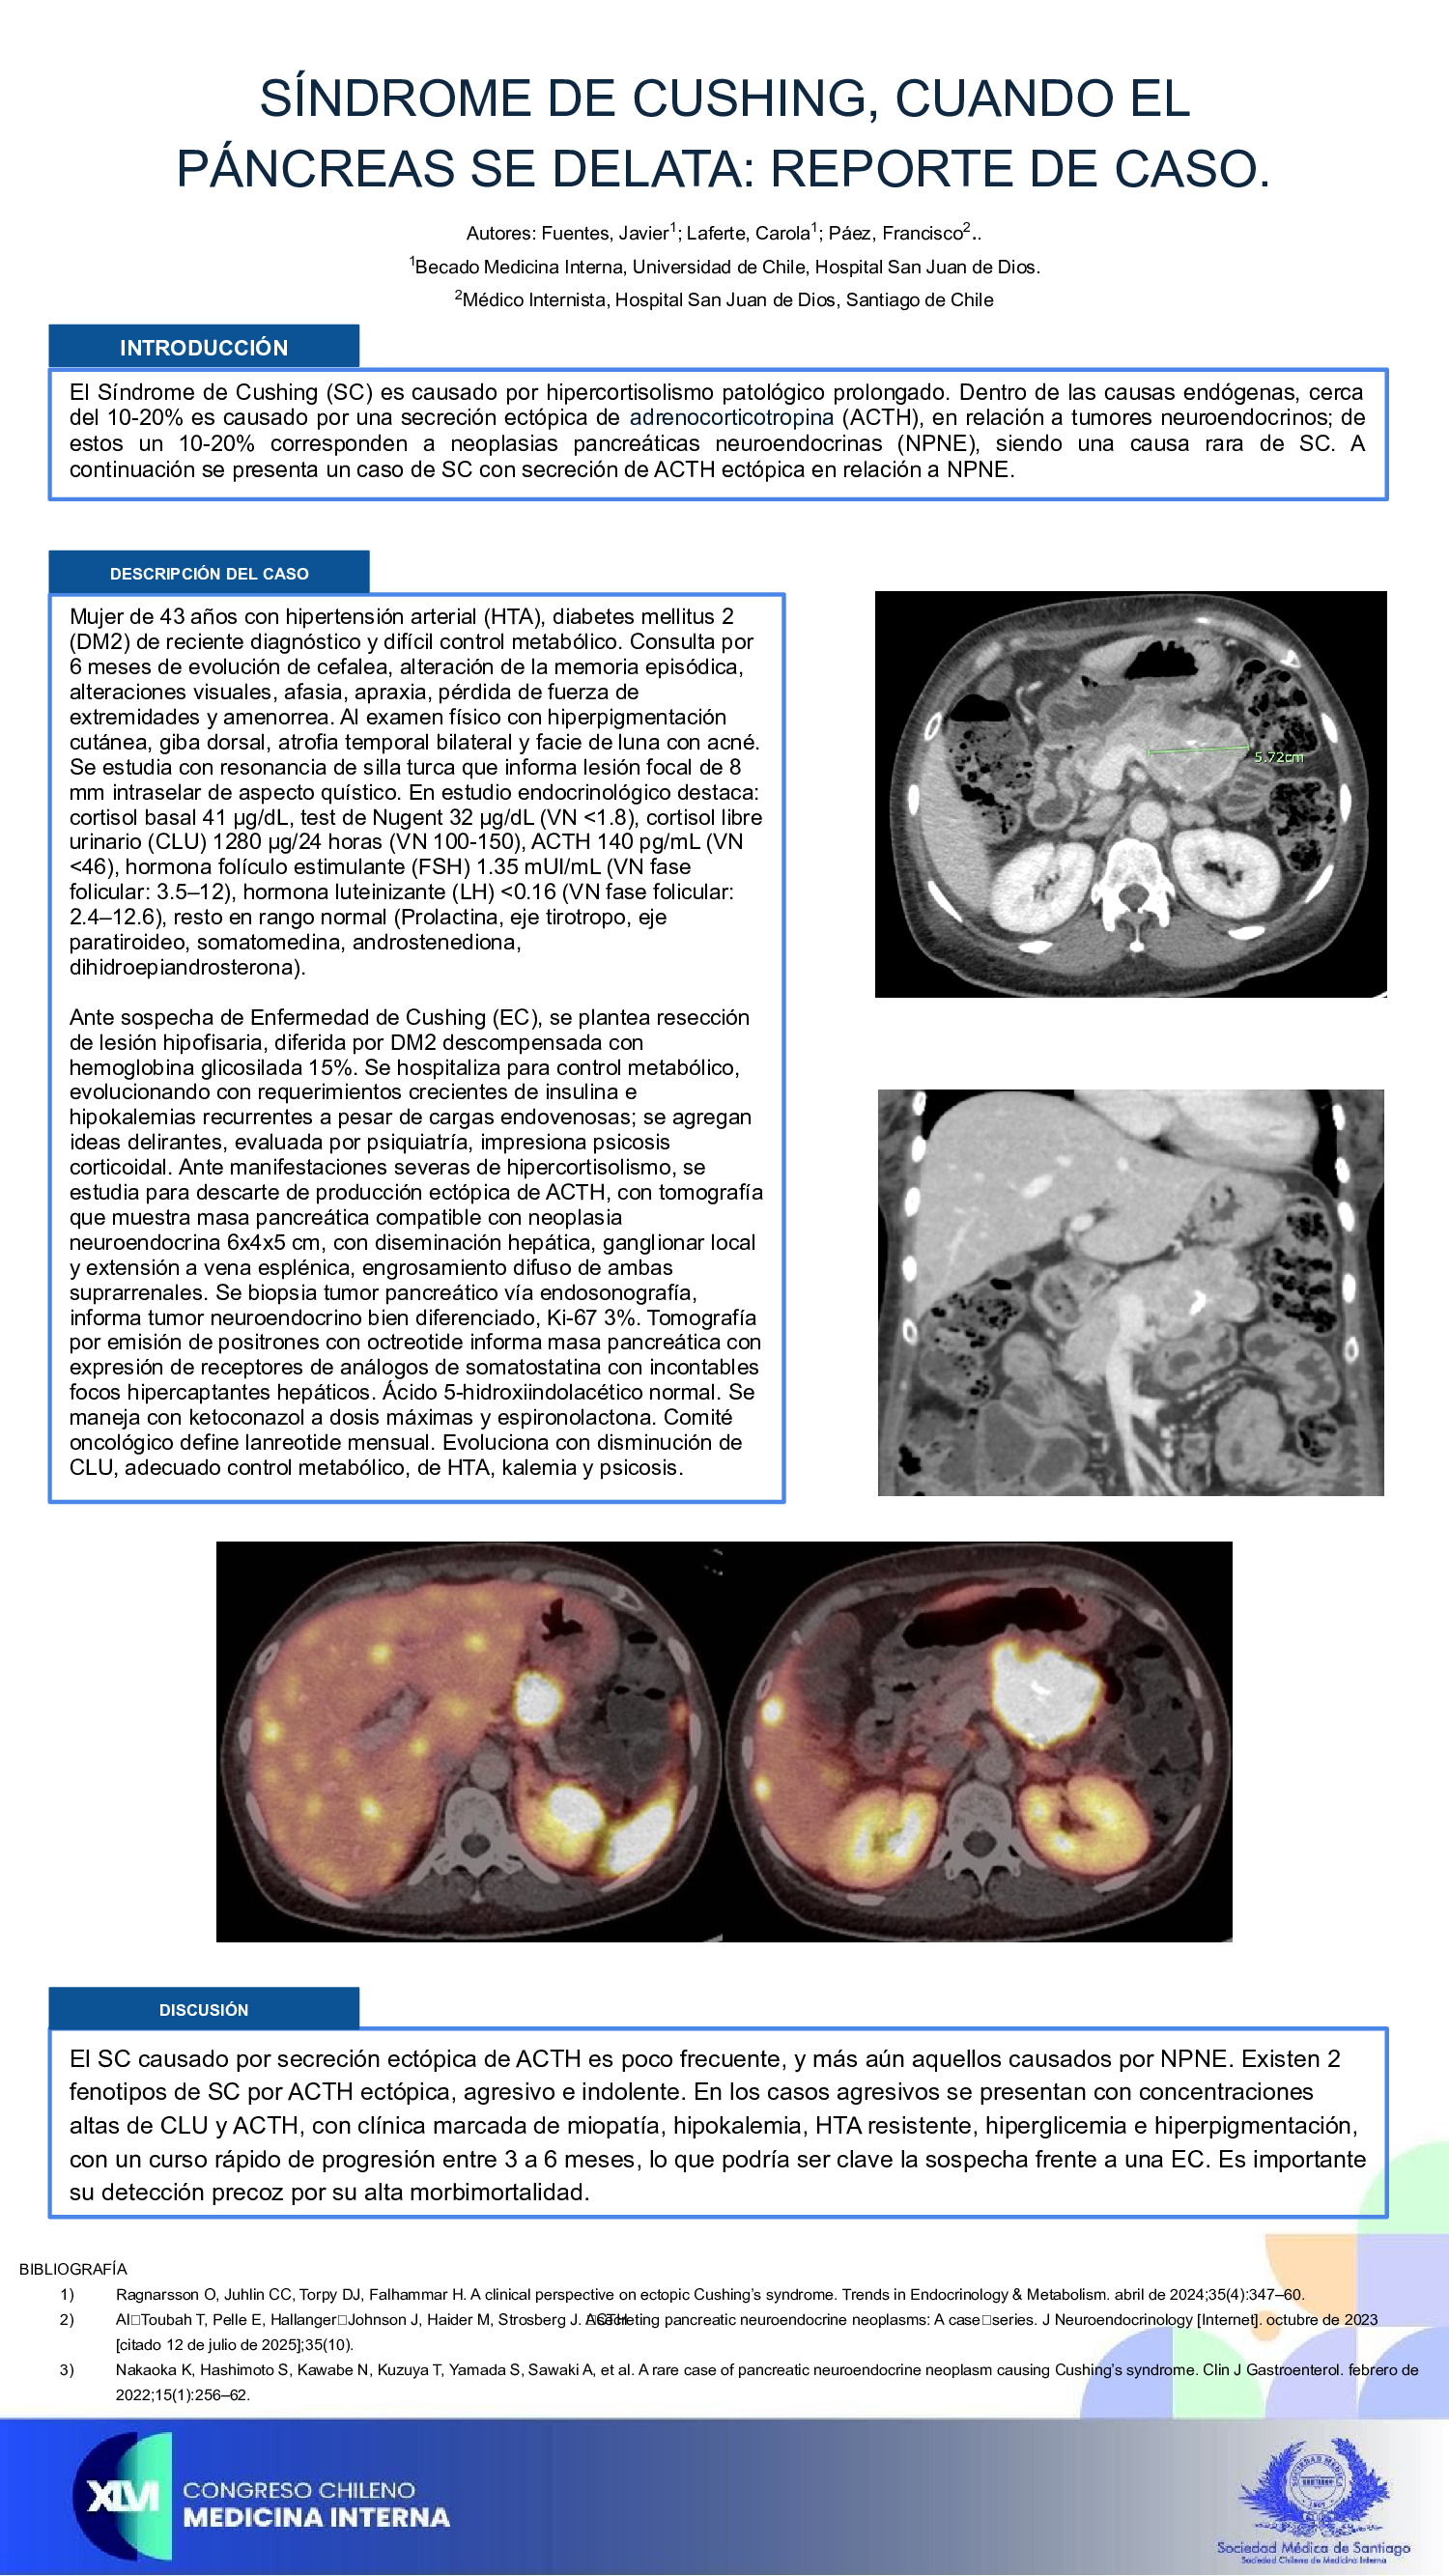

SÍNDROME DE CUSHING, CUANDO EL PÁNCREAS SE DELATA: REPORTE DE CASO.

Javier Fuentes Yévenes, Carola Laferte, Francisco Páez